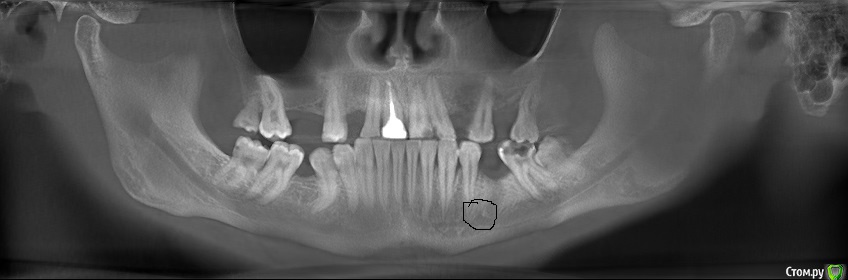

erm Опубликовано 2 февраля, 2016 Автор Поделиться Опубликовано 2 февраля, 2016 вот панарамный снимок 2014 года. второго зуба уже у меня нет, он был в 2015 удален Ссылка на комментарий

erm Опубликовано 2 февраля, 2016 Автор Поделиться Опубликовано 2 февраля, 2016 во еще снимок из клкт Ссылка на комментарий